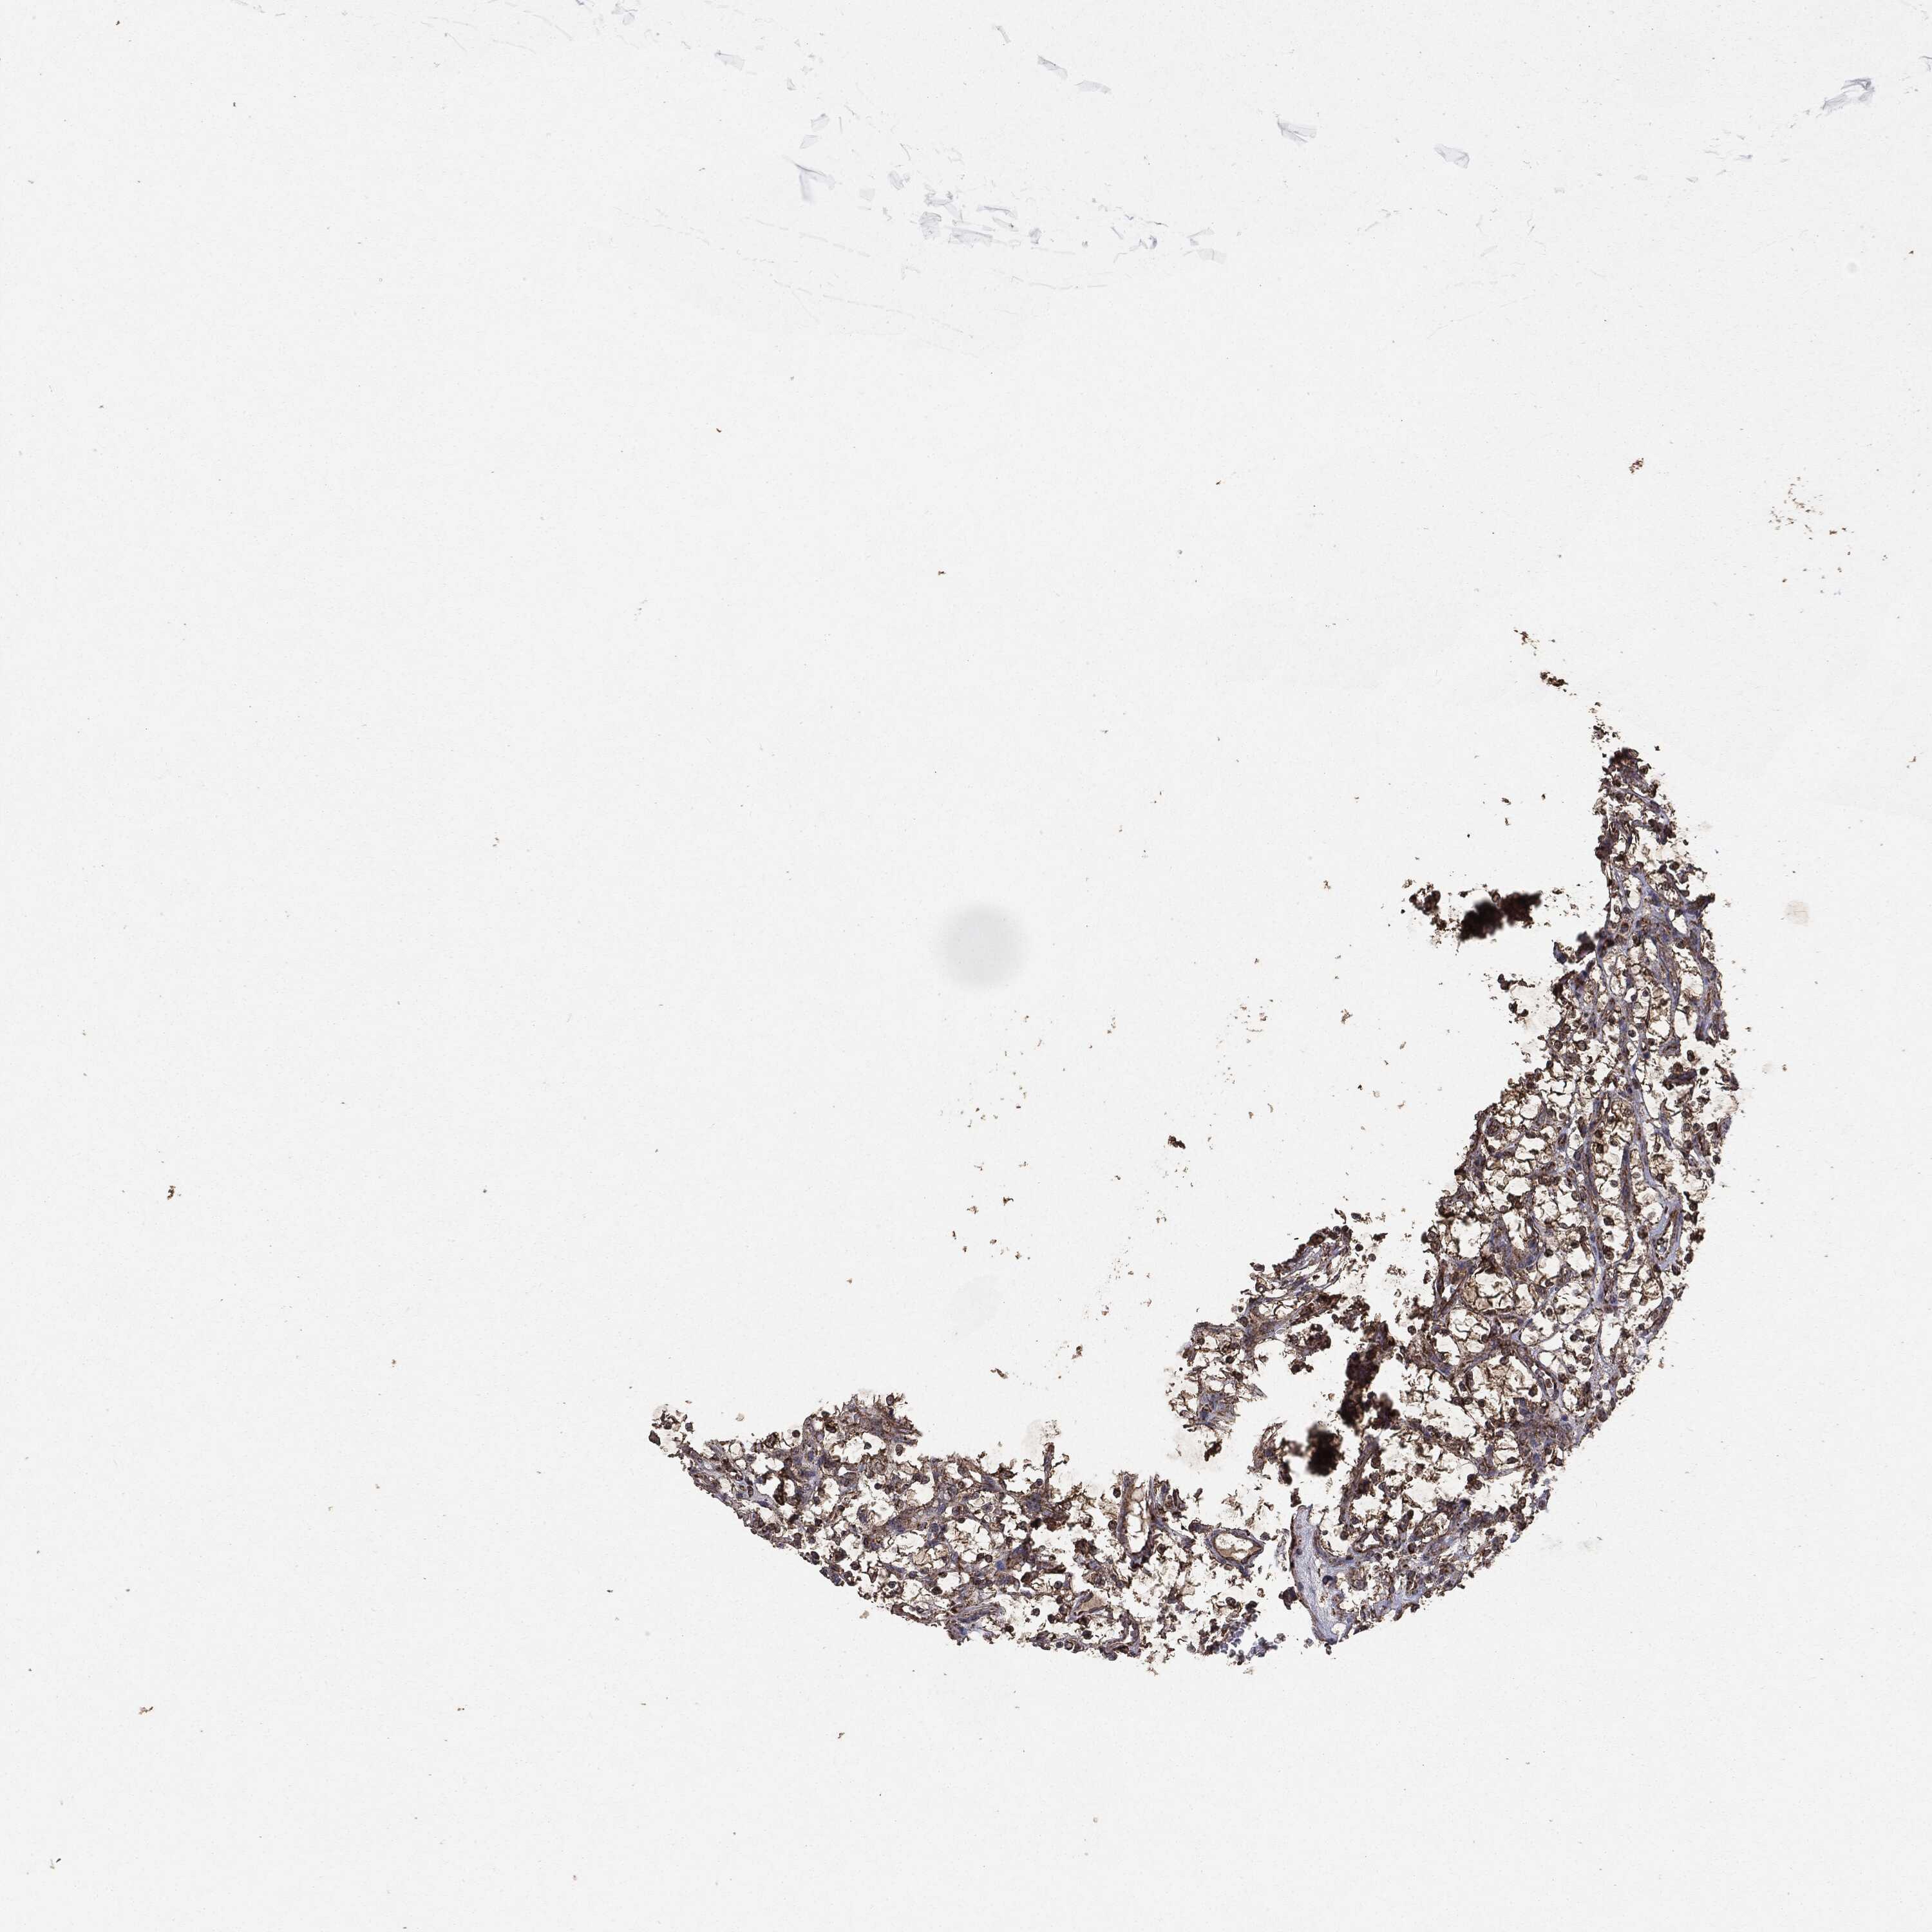

KIDNEY RENAL CLEAR CELL CARCINOMA (VALIDATION) - Interactive survival scatter ploti

The Survival Scatter plot shows the clinical status (i.e. dead or alive) for all individuals in the patient cohort, based on the same data that underlies the corresponding Kaplan-Meier plots. Patients that are alive at last time for follow-up are shown in blue and patients who have died during the study are shown in red.

The x-axis shows the expression levels (FPKM) of the investigated gene in the tumor tissue at the time of diagnosis. The y-axis shows the follow-up time after diagnosis (years). Both axes are complimented with kernel density curves demonstrating the data density over the axes. The top density plot shows the expression levels (FPKM) distribution among dead (red) and alive patients (blue). The right density plot shows the data density of the survived years of dead patients with high and low expression levels respectively, stratified using the cutoff indicated by the vertical dashed line through the Survival Scatter plot. This cutoff is automatically defined based on the FPKM cutoff that minimizes the p-score. The cutoff can be changed by dragging the vertical line or by entering a cutoff value in the square labeled "Current cut-off".

Under the Survival Scatter plot the p-score landscape (black curve; left axis) is shown together with dead median separation (red curve; right axis). Dead median separation is the difference in median mRNA expression between patients who have died with high and low expression, respectively. It is calculated as follows: median FPKM expression of dead patients with high expression - median FPKM expression of dead patients with low expression. This is intended to aid the user in visually exploring custom cutoffs and the associated p-scores and dead median separation.

Individual patient data is displayed and can be filtered by clicking on one or more of the category buttons on the top of the page. Categories describing expression level and patient information include: high, low, alive, dead, female, male and tumor stages. The scale of the x-axis can be toggled between linear and log-scale by clicking on the "x log" button. Mouse-over function shows TCGA ID, patient information and mRNA expression (FPKM) for each patient.

& Survival analysisi

Kaplan-Meier plots summarize results from analysis of correlation between mRNA expression level and patient survival. Patients were divided based on level of expression into one of the two groups "low" (under cut off) or "high" (over cut off). X-axis shows time for survival (years) and y-axis shows the probability of survival, where 1.0 corresponds to 100 percent.

MTOR is not prognostic in Kidney Renal Clear Cell Carcinoma (validation)

Best expression cut offi

Based on the FPKM value of each gene, patients were classified into two groups and association between prognosis (survival) and gene expression (FPKM) was examined. The best expression cut-off refers the FPKM value that yields maximal difference with regard to survival between the two groups at the lowest log-rank P-value. Best expression cut-off was selected based on survival analysis .

When clicking on this number, the vertical dashed line indicating cut-off, the interactive survival plot, and the Kaplan-Meier curve will be adjusted to show results based on the best expression cut-off.

: 11.8

P scorei

Log-rank P value for Kaplan-Meier plot showing results from analysis of correlation between mRNA expression level and patient survival.

N/A

5-year survival highi

5-year survival for patients with higher expression than the expression cutoff.

For melanoma and glioma, 3-year survival is shown.

5-year survival lowi

5-year survival for patients with lower expression than the expression cutoff.

TCGA RNA samplesi

RNA-seq data is reported as average FPKM (number Fragments Per Kilobase of exon per Million reads), generated by the The Cancer Genome Atlas (TCGA) .

Normal distribution across the dataset is visualized with box plots, shown as median and 25th and 75th percentiles. Points are displayed as outliers if they are above or below 1.5 times the interquartile range. FPKM values of the individual samples are presented next to the box plot.

Average pTPM 12.9

Number of samples 100